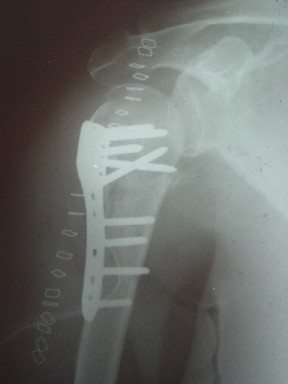

Висеть будет красиво. У людей физически активного периода жизни нужно открыть, восстановить костную анатомию и восстановить сухожильный аппарат.

В этом плане Locking plate очень хороша так как позволяет начать движения сразу после операции.

Клинические снимки - 3 недели после операции

с уважением М. Беренштейн